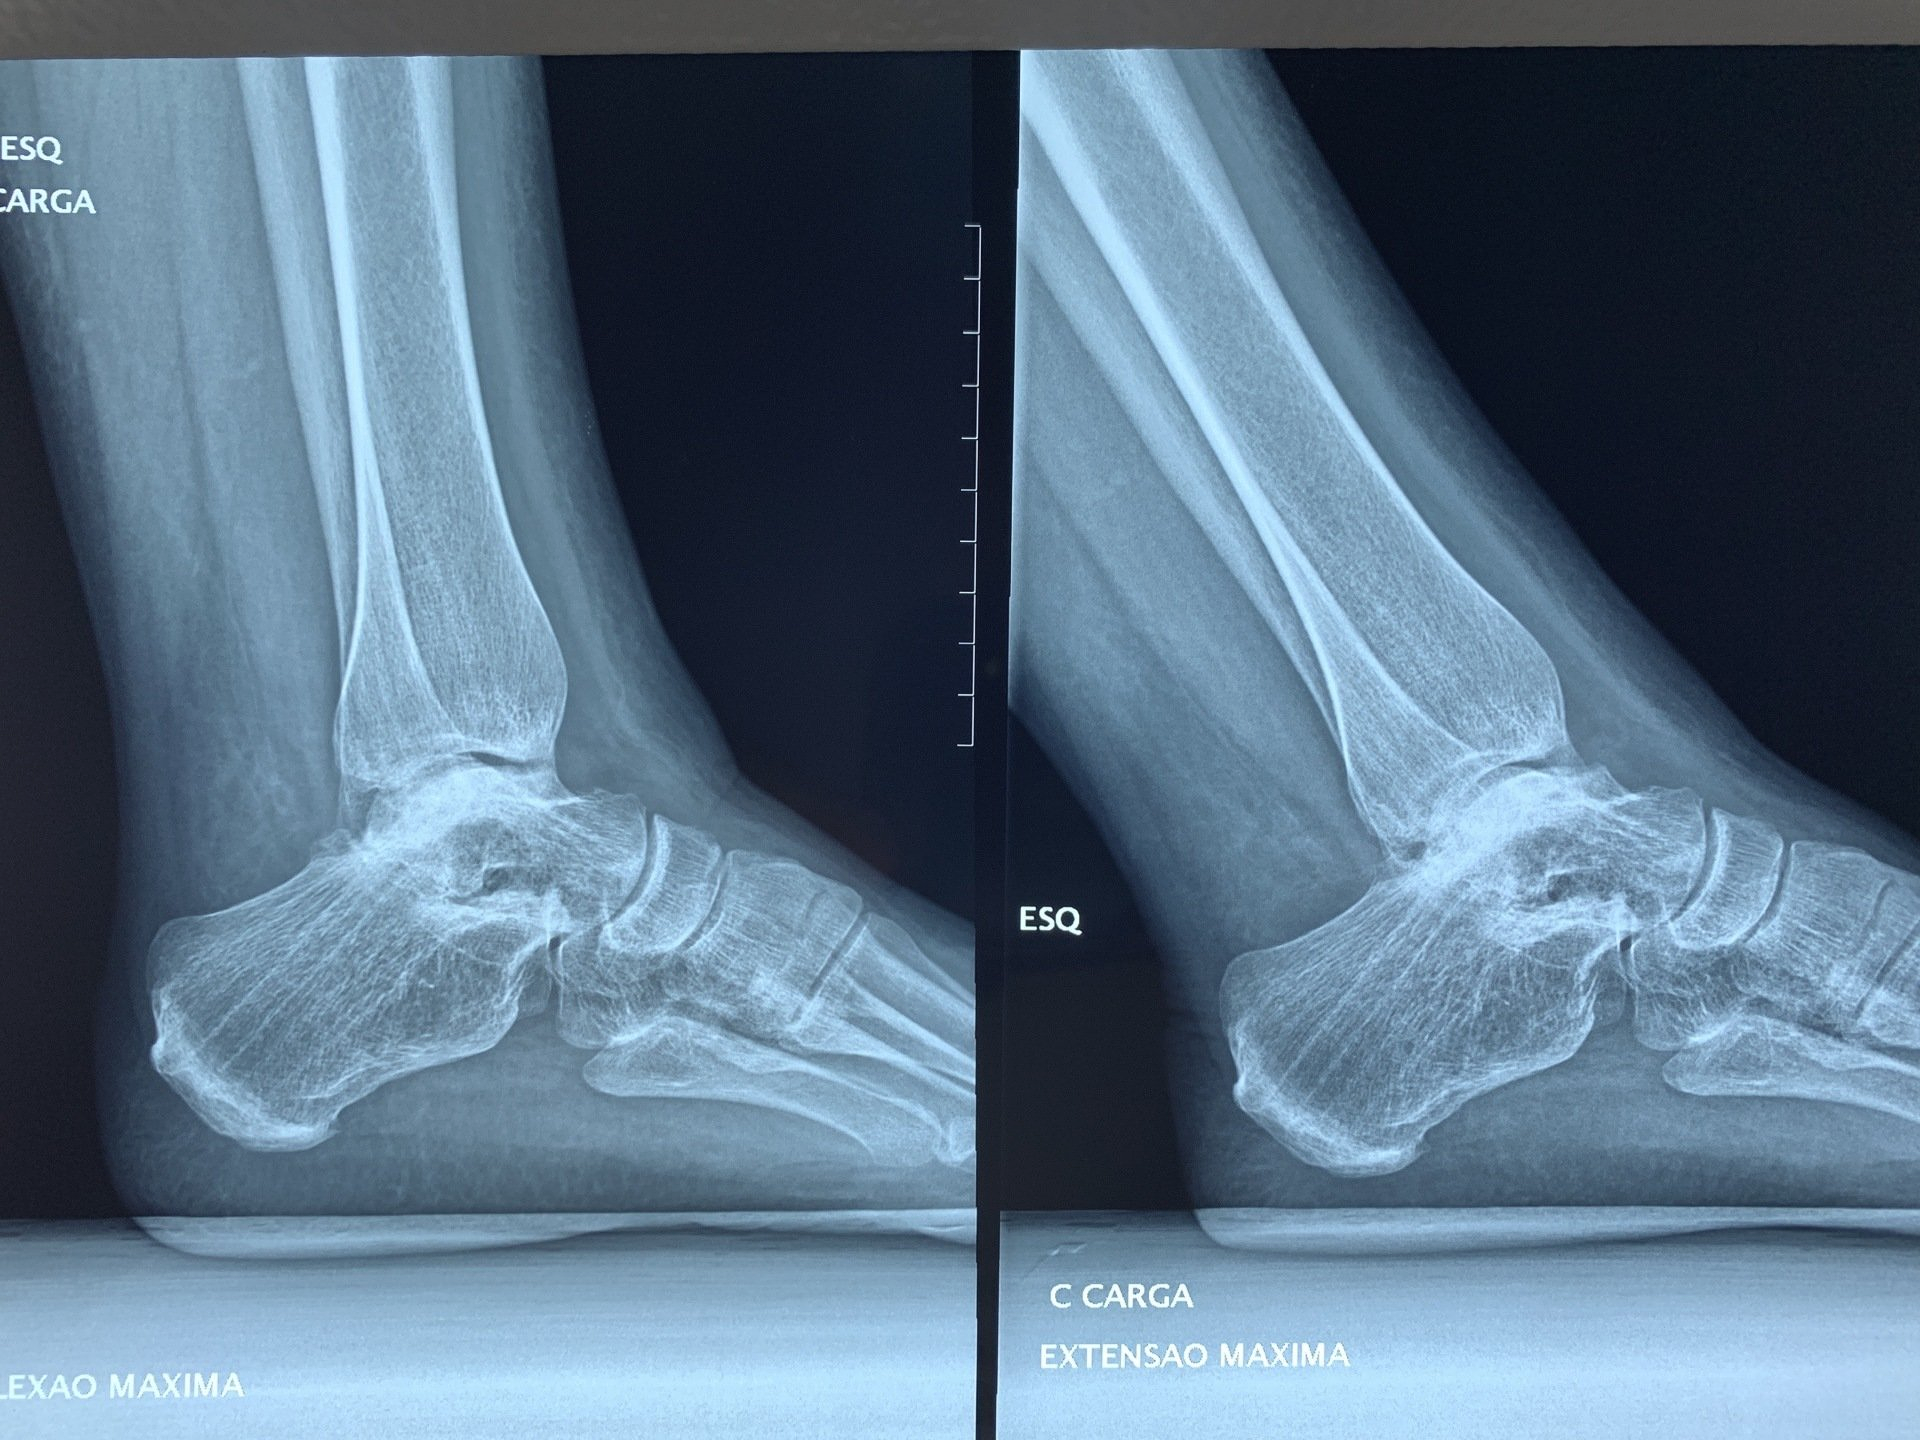

05/12/2020: As fraturas do tornozelo podem levar a um processo degenerativo chamado de artrose ou osteoartrose. O estágio final desta doença se caracteriza por dor e limitação da marcha. Uma das soluções de tratamento é a Artroplastia Total do Tornozelo ou prótese de tornozelo, que tem o objetivo de eliminar a dor e devolver a função. Este sábado podemos realizar mais uma prótese de tornozelo para tratamento de um quadro de osteoartrose pós-traumática.

Paciente do Paraguai foi submetido a Artroplastia Total do Tornozelo neste último sábado no Hospital Viver de Ribeirão Preto com o Dr Rogério Bitar e o Dr Alexandre Leme Godoy dos Santos. O paciente optou pela artroplastia após ter passado por diversos médicos que sugeriram fazer a fusão do tornozelo. O paciente segue em recuperação.